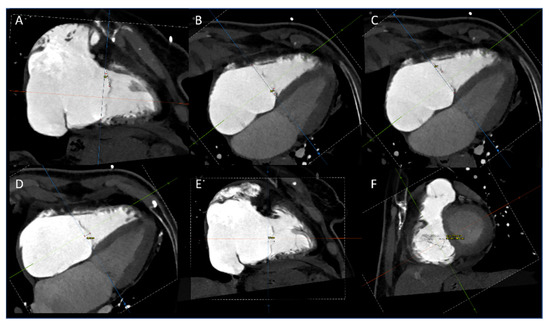

2.2. CT Acquisition

2.3. CT Data Analysis